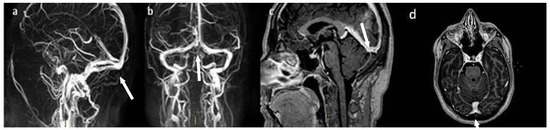

2. Case Presentation